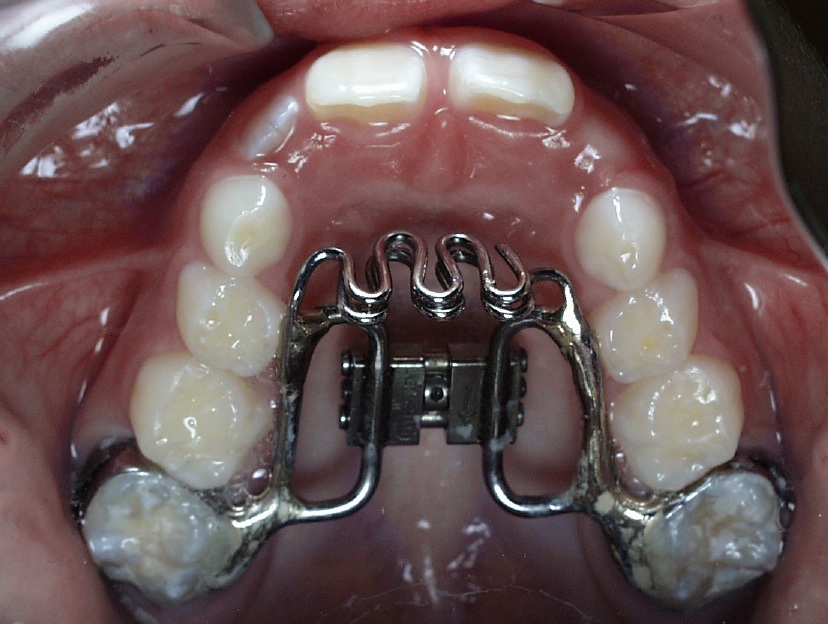

The cheeks push the UPPER back teeth IN, causing a narrowed

palate, while the tongue posture is LOW, so no balance of forces occurs on the upper teeth (as seen in the lower teeth) |

treatment will be a short 8-10 month duration and will consist of only 1

appliance to prevent the thumb from sneaking in the mouth (especially at night

which is the hardest to control!)

expander, or just a regular thumb crib.

crib? Dr. Bauer will explain all of this

to you- if your child has a crossbite, he or she will need the expander as

well.